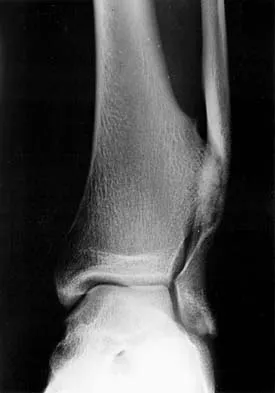

Question 15 High Yield

Figure 36a shows the current radiograph of a 65-year-old woman who slipped and fell. History reveals that prior to the fall she was actively functioning without pain. Figure 36b shows a radiograph obtained 1 year ago. Based on the fracture pattern, the failure is most likely related to

Detailed Explanation

The radiograph shows a fracture distal to the prosthesis in a stable, apparently well-fixed prosthetic stem. The well-fixed prosthesis-bone composite is stiff, creating a modulus mismatch between the proximal and distal femur. Therefore, the risk of fracture, particularly in osteoporotic bone, is increased at this level. Revision of the stem to a longer construct is unnecessary, and standard plate and screw fixation has been shown to yield union rates of greater than 90%. Nonsurgical treatment of fractures distal to the tip of the prosthesis results in high nonunion rates, reported to be from 25% to 42%. Johansson JE, McBroom R, Barrington TW, Hunter GA: Fracture of the ipsilateral femur in patients with total hip replacement. J Bone Joint Surg Am 1981;63:1435-1442. Bethea JS III, DeAndrade JR, Fleming LL, Lindenbaum SD, Welch RB: Proximal femoral fractures following total hip arthroplasty. Clin Orthop 1982;170:95-106.